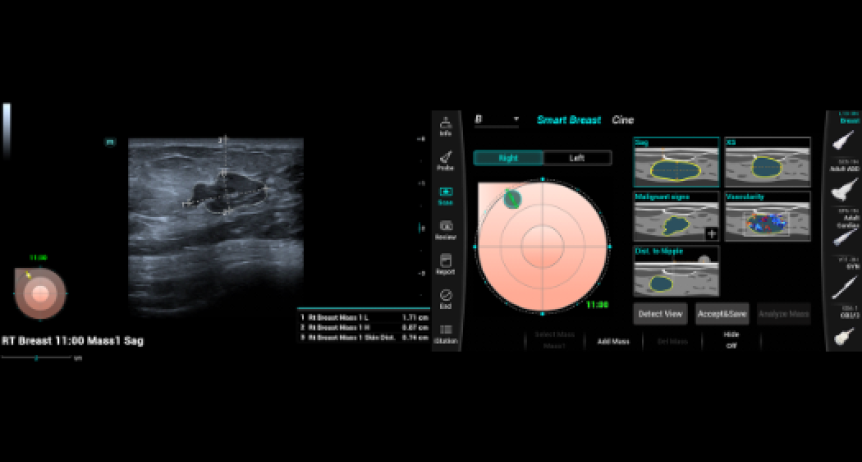

SMART BREAST